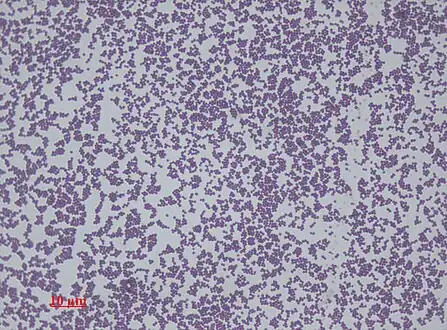

Scanning electron image of S. epidermidis.

Staphylococcus epidermidis is a very hardy microorganism, consisting of nonmotile, Gram-positive cocci, arranged in grape-like clusters. It forms white, raised, cohesive colonies about 1–2 mm in diameter after overnight incubation, and is not hemolytic on blood agar.[5] It is a catalase-positive,[7] coagulase-negative, facultative anaerobe that can grow by aerobic respiration or by fermentation. Some strains may not ferment.[3][8]